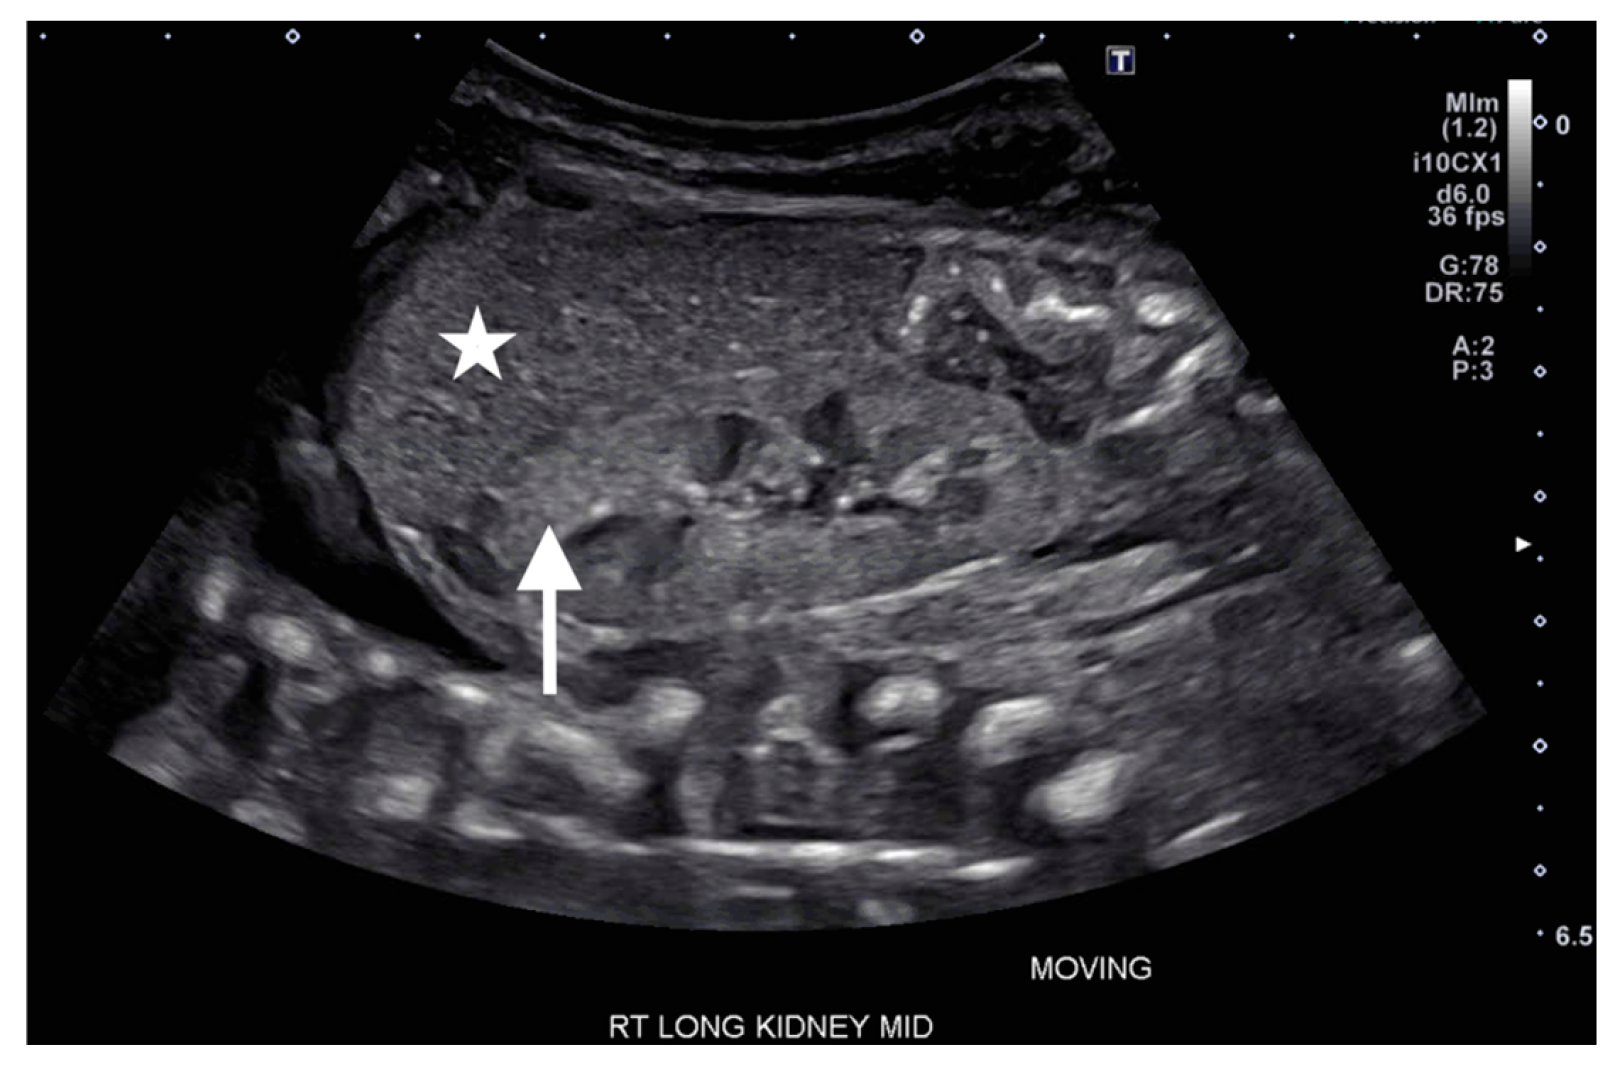

On DOL 5, the patient developed worsening abdominal distention with increased free fluid, rising lactate level, and continued oliguria with minimal brown-colored output, indicating potential bladder rupture. Renal ultrasound at that time demonstrated structurally normal kidneys and ureters, with contusive injuries in the parenchyma (Figure 1 and Figure 2). Pediatric urology was consulted. Diagnostic paracenteses and non-voiding cystogram showed no urinary leak. Computed tomography (CT) of the abdomen and pelvis was performed to further evaluate for free fluid or perforated viscus showed no renal contusion, but noted both kidneys had patchy opacification in the capsule and medulla, consistent with bilateral renal cortical necrosis (Figure 3). Cranial ultrasound was also performed at this time and showed focal parenchymal hemorrhage in the posterior portion of the left frontal lobe (Figure 4).

Figure 1.

Ultrasound of right kidney on day of life 5 showing increased echogenicity (arrow) compared to that of the adjacent liver (asterisk).